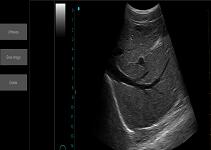

Ultrasound Scan Equipment Portable Ultrasound Scanner Ipad Ultrasound Machine with Probes of 2~15MHz

| 1. | Superior Image Quality | Incredible image quality helps you make fast and precise decision |

Images

Ultrasound Scan Equipment Portable Ultrasound Scanner Ipad Ultrasound Machine with Probes of 2~15MHz Images |